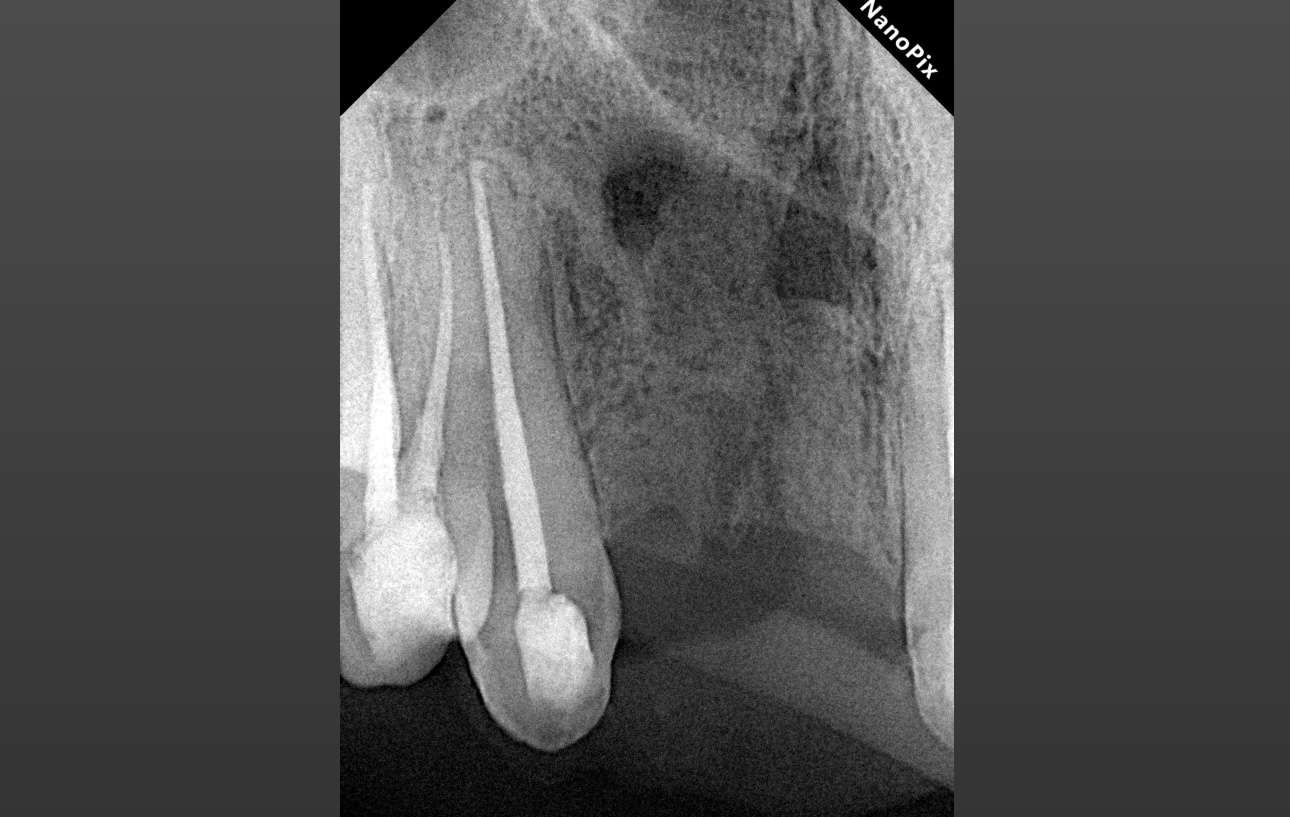

Ирригация 3% NaOCl с УЗ активацией + 17% ЭДТА.

Обтурация биокерамическим силером с гуттаперчей. Автор: Диана Кипарисова